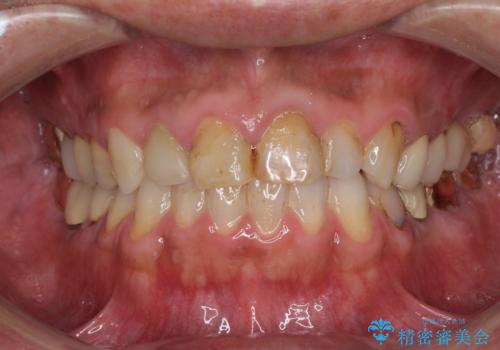

かぶせものと歯ぐきの境目が黒い 40代女性

保険のかぶせ物・詰め物を金属を使わないセラミックへ 自然な見た目へ